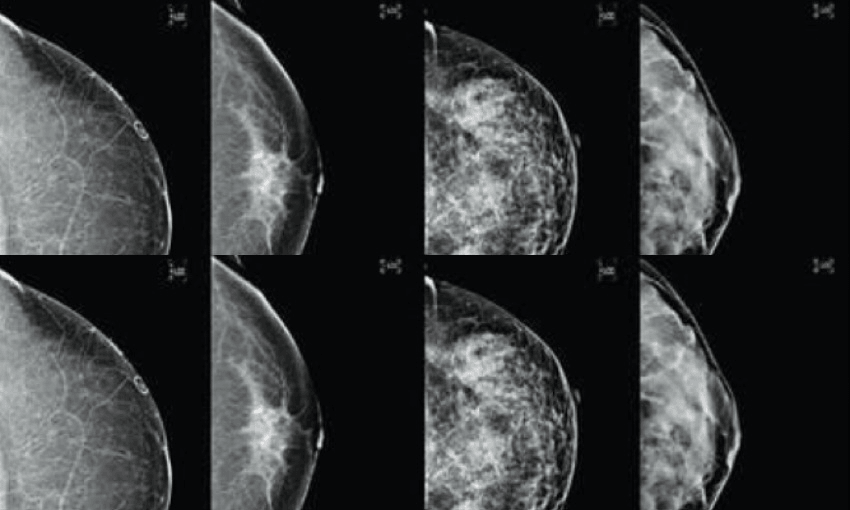

For women, like Sowerby, who have dense breasts – where there is a higher proportion of fibrous, supportive, tissue compared with fatty tissue – that density may mask cancers. Both dense tissue and cancer cells show up white on a mammogram, making it harder to interpret for the radiographer.